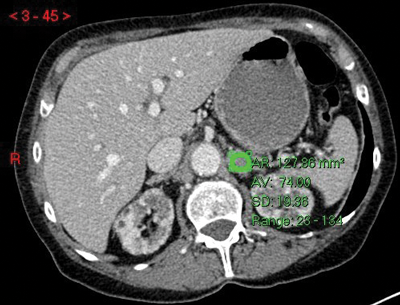

Figure 3:

Top: Unenhanced CT (HU 23).

Centre: Arterial phase CT (HU 74).

Bottom: Delayed phase CT (HU 37).

Absolute washout = (74-37)/(74-23)x100 = 37/51x100 = 72.5% in keeping with adenoma.